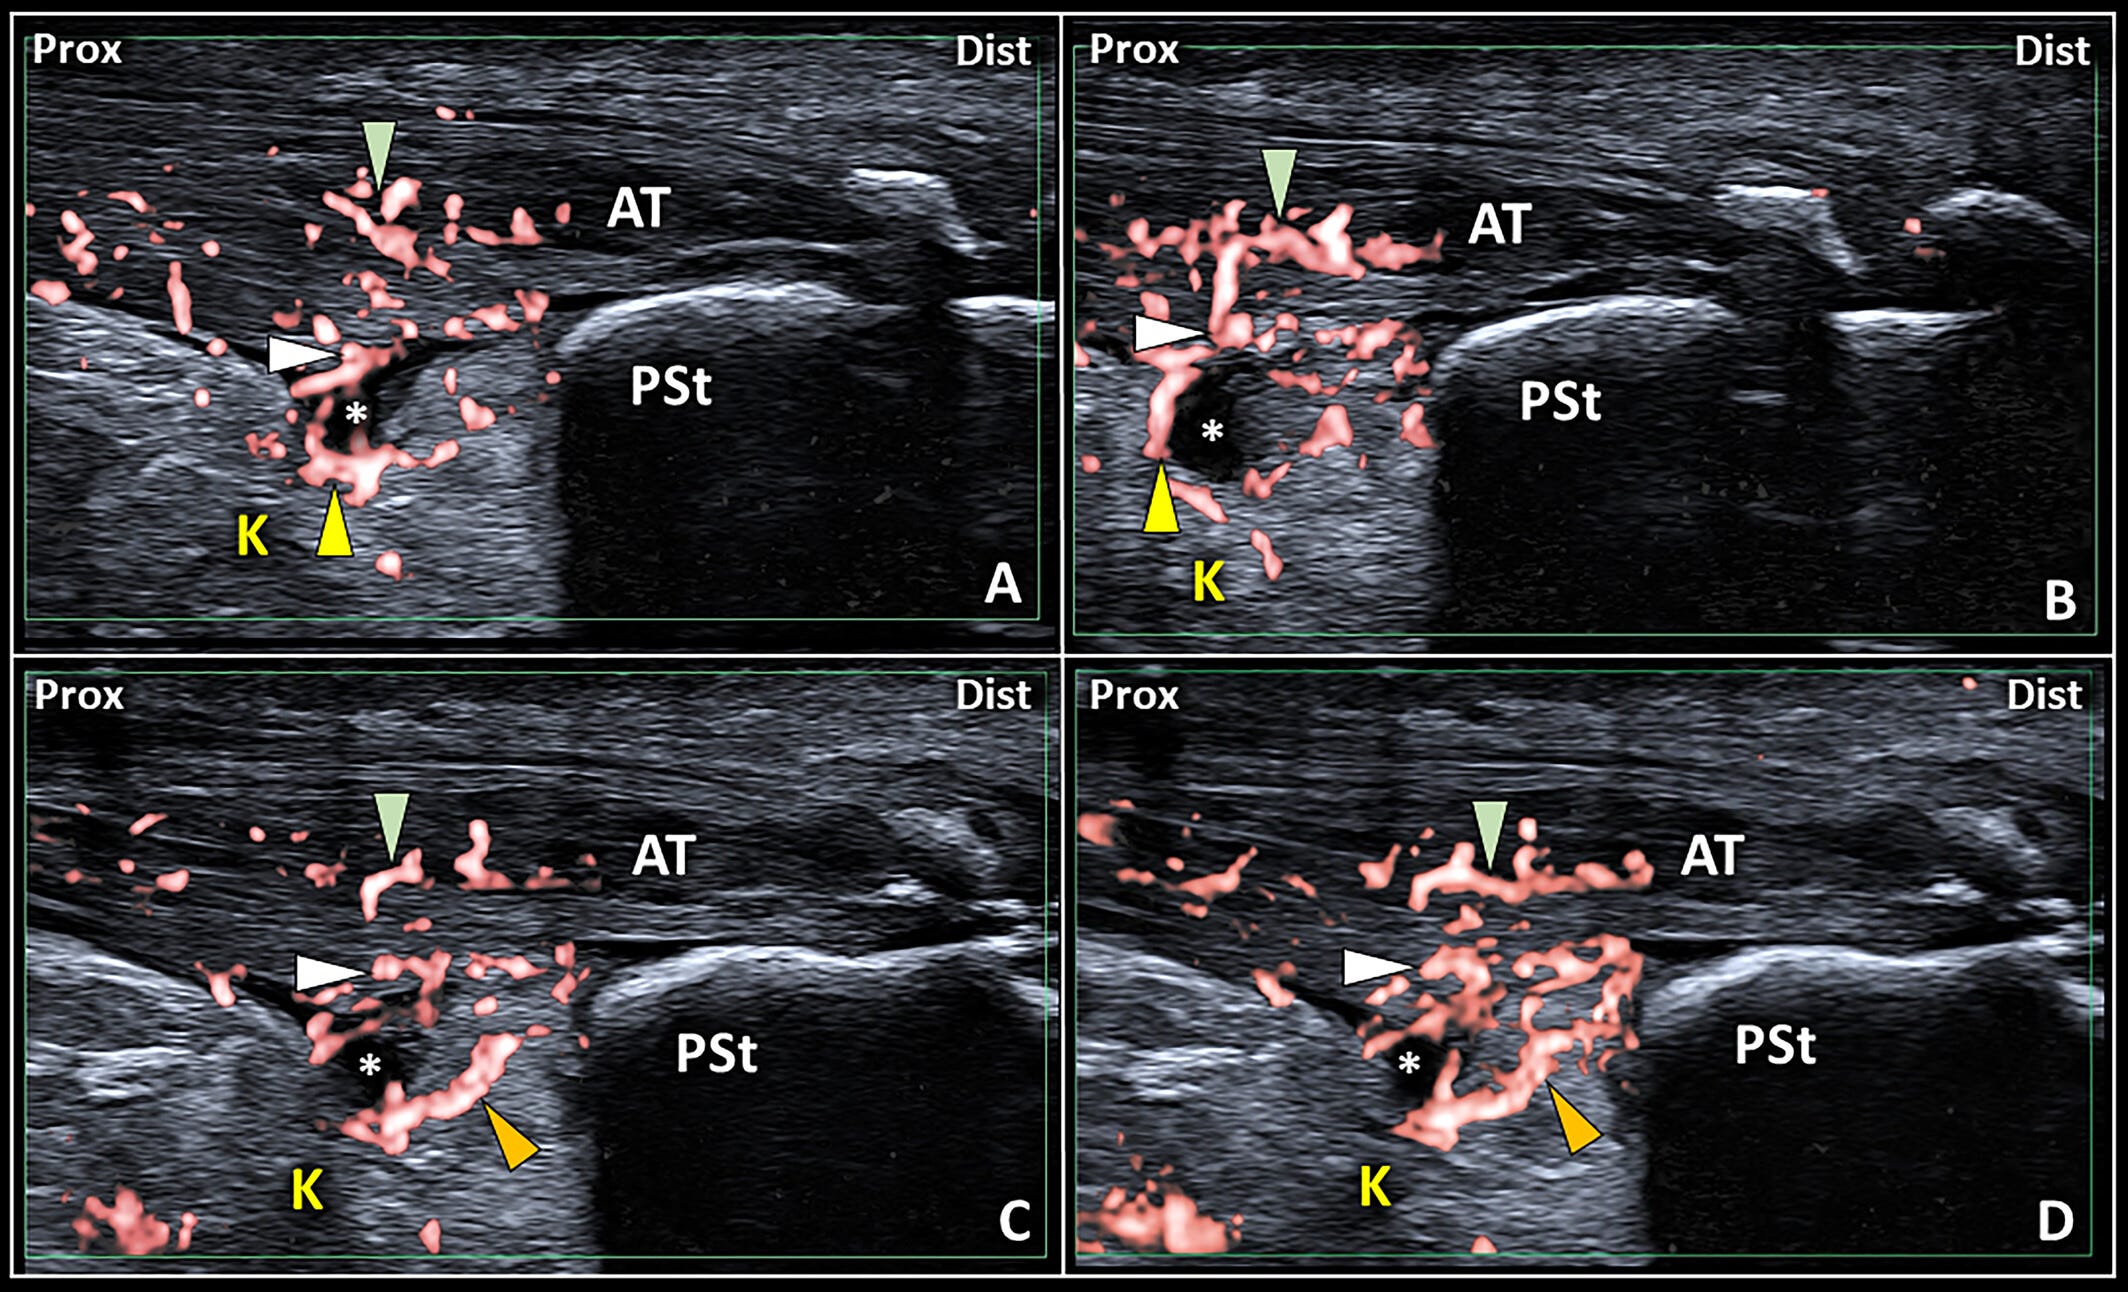

Patrones ecográficos de la interfaz bursa retrocalcánea–tendón de Aquiles.

En condiciones normales (A), la cuña posteroinferior (PIW) de la almohadilla grasa de Kager (K) (asterisco amarillo) contacta con la superficie profunda del tendón de Aquiles (AT).

Por el contrario, un derrame anecoico localizado en el receso posterior de la bursa retrocalcánea (RCB) (B) puede desplazar la cuña grasa (asterisco amarillo) y mostrar una interfaz lineal bursa–tendón (puntas de flecha vacías).

En pacientes con disrupción de las fibras profundas del tendón (asterisco blanco), la interfaz bursa–tendón irregular y mal definida (C y D) presenta digitaciones sinoviales de la RCB (puntas de flecha blancas) que penetran en el tendón de Aquiles.

Dist: distal; Prox: proximal;

PSt: tuberosidad posterosuperior del calcáneo.

Se observan señales vasculares dentro del tejido tendinoso (punta de flecha verde) del tendón de Aquiles (AT), del fibrocartílago que recubre su superficie profunda (punta de flecha blanca) y del tejido sinovial (punta de flecha amarilla) del receso posterior de la bursa retrocalcánea (RCB) (asterisco blanco) (A y B).

En el mismo paciente con tendinopatía aquílea insercional (IAT) (C y D), la hipervascularización también afecta a la cuña posteroinferior (PIW) de la almohadilla grasa de Kager (punta de flecha naranja).

Dist: distal; K: almohadilla grasa de Kager; Prox: proximal;